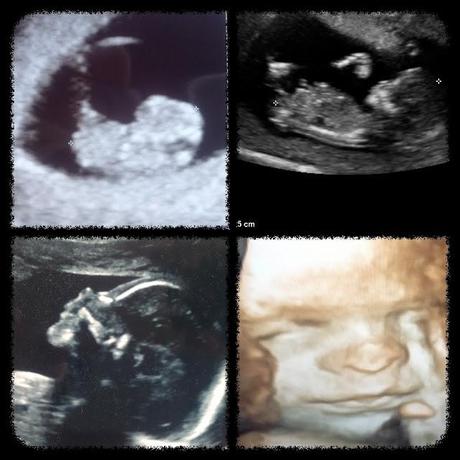

Ricerco nei tuoi tratti riflessi dall’ecografia qualcosa che rimandi a me o a tuo padre,

ma poi mi perdo nelle pieghe delicate del tuo viso,

i lievi declivi, le piccole fossette,

e perdo noi per trovare solo te.